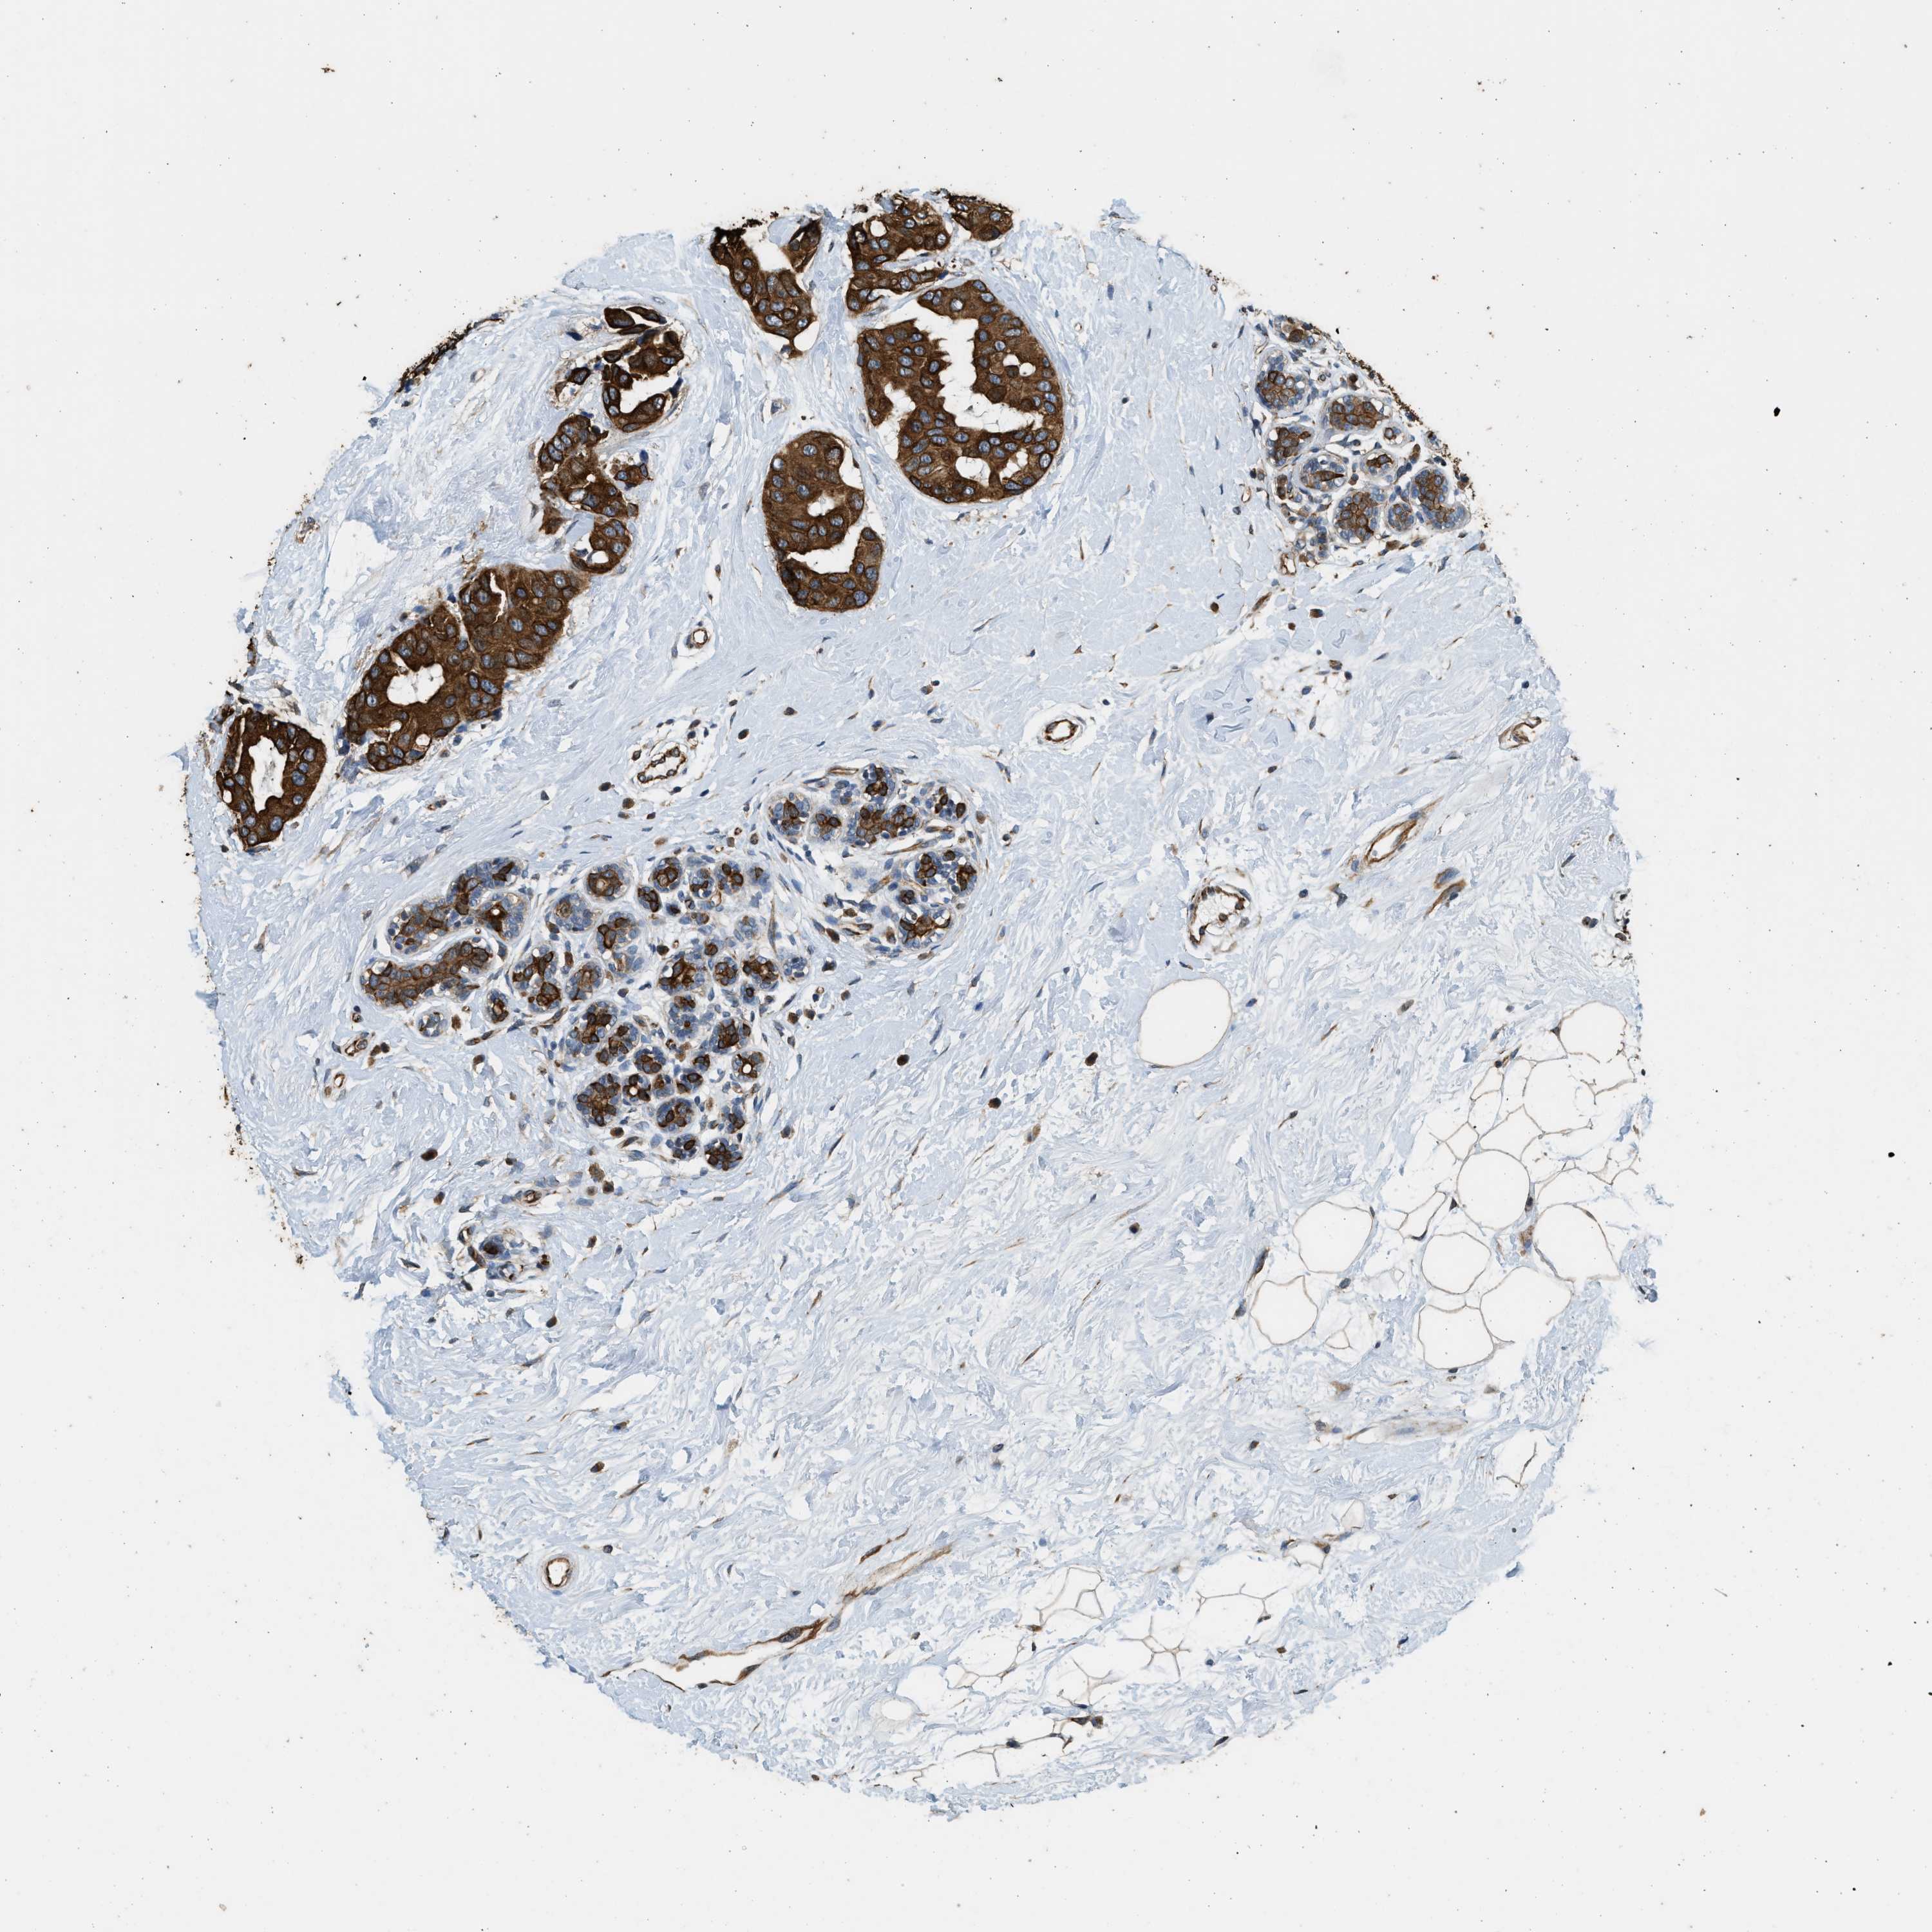

CANCER BREAST CANCER Show tissue menu

BRCA TCGA BRCA VALIDATION PROTEIN EXPRESSION